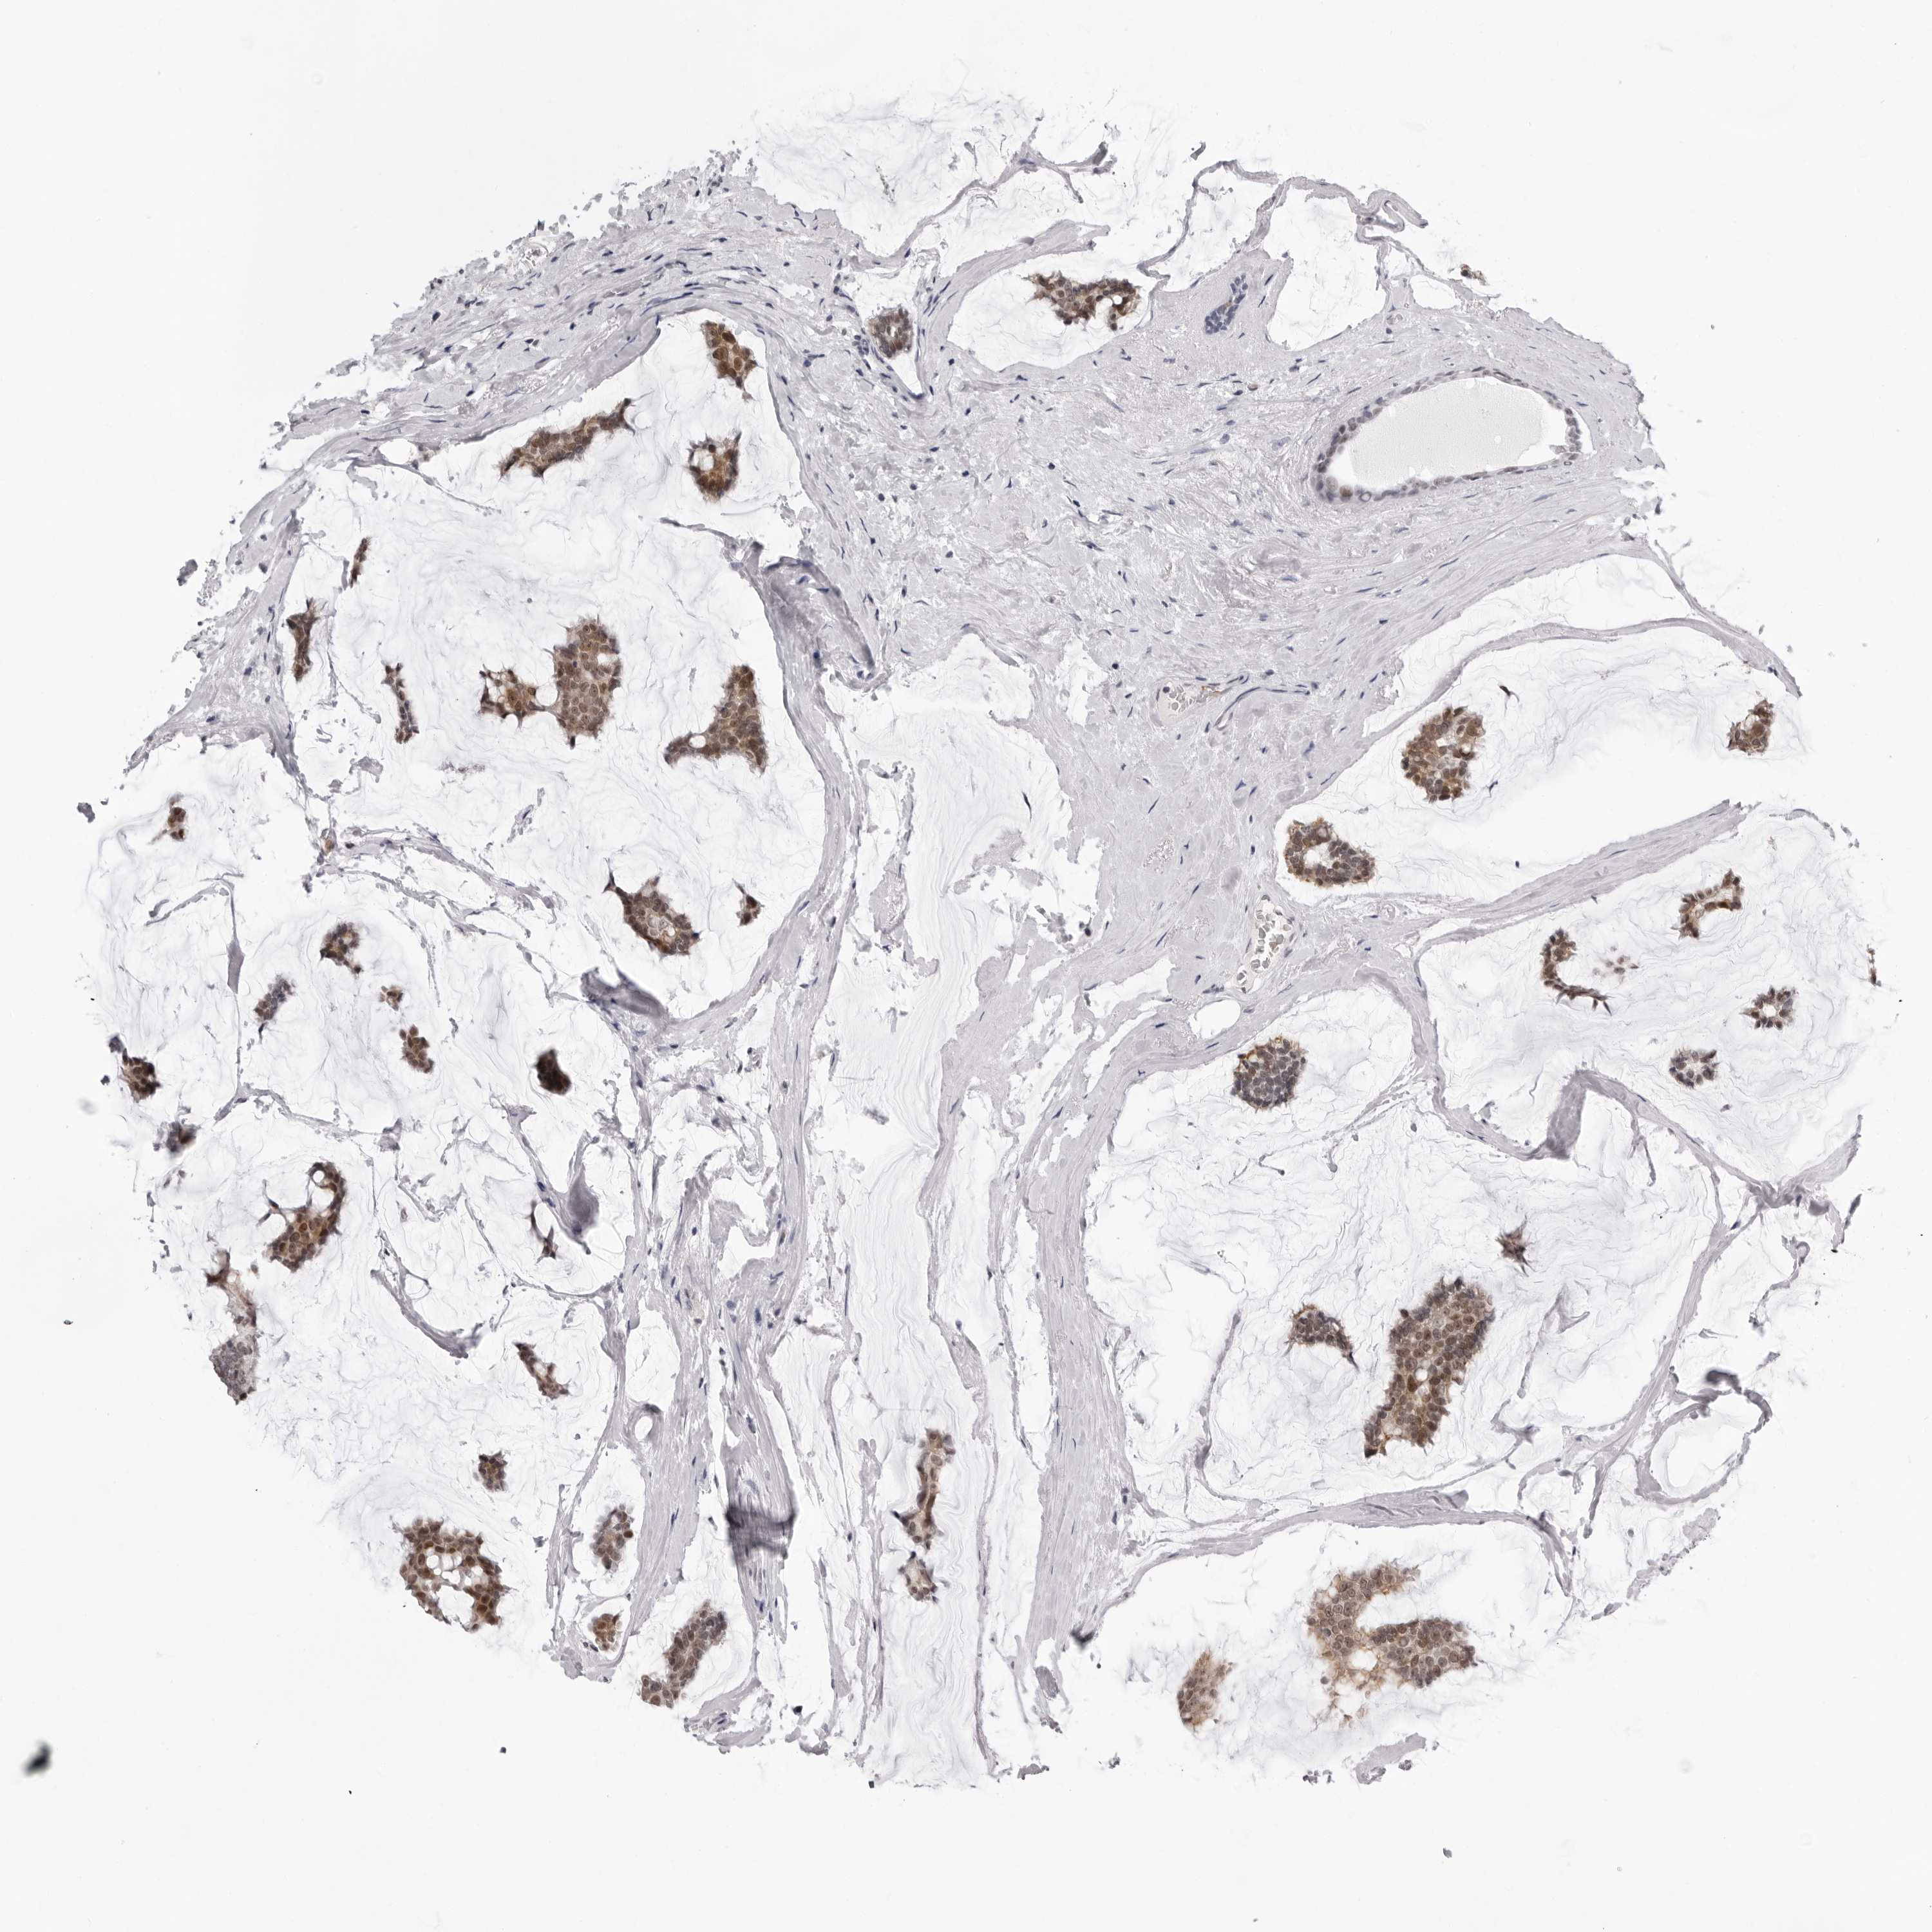

BRCA TCGA BRCA VALIDATION PROTEIN EXPRESSION

ANTIBODIES

AND

VALIDATION